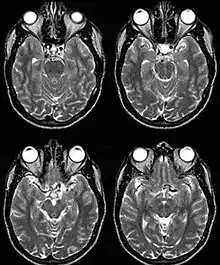

Internal carotid artery dolichoectasia is particularly interesting because the artery normally already contains one hairpin turn. Seen in an MRI as two individual arteries at this hairpin, a carotid artery dolichoectasia can progress so far as to produce a second hairpin turn and appear as three individual arteries on an MRI. In the case of a dolichoectasia of the Internal Carotid Artery (ICD), the pathogenesis is primarily related to compression of the optic nerves at the optic chiasma (see Fig. 1 and 2).